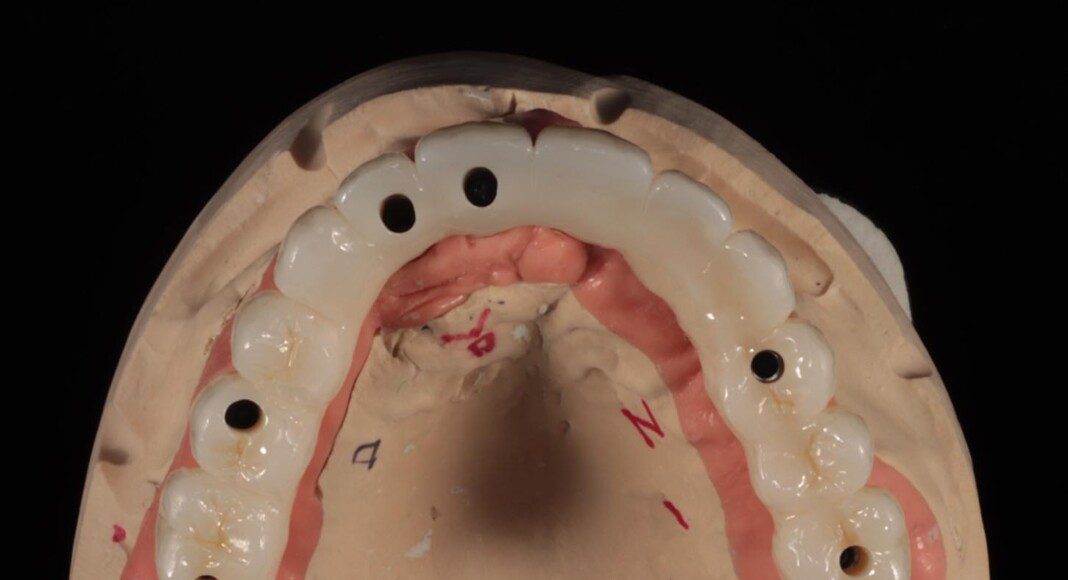

Prototype try-in. This patient was much more particular than we expected. Therefore, we made a very detailed prototype for everyone to evaluate closely. Pictures taken from all angles.

Zirconia bridge cemented to the titanium cylinders (tissue view) + one cemented unit on one old implant. The angle of this implant was too far forward. By cementing this one, we can still use it for retention and stability. Note the convex nature of the tissue interface for easy cleaning.